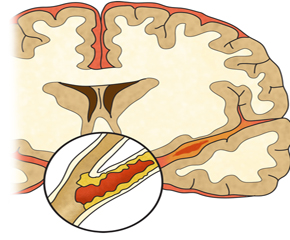

이번 포스팅에서 뇌경색 초기증상 모두 알아보려고 해요. 한 번쯤은 뇌경색, 뇌출혈, 뇌졸중에 대해서 들어보신 적이 있을꺼에요.

특별한 변화 없이 가만히 있다는데 땅이 움직이거나 주위의 사물이 돌아가는 느낌이 드는 등 어지럼증이 연속된다면 뇌경색 초기증상을 의문스러워해 볼 수 있습니다. 뇌경색으로 인해 혈액이 제대로 전달되지 못해 뇌가 정상적으로 작동하지 않아 생기는 증상이고요.

뇌경색 초기증상이 의심된다면 지금 바로 병원을 내방해 진단을 받고 적절한 치료를 손대는 것이 후유증을 감하는데 중요 해요. 시간이 관건이며, 뇌세포의 괴사, 증상 악화, 너무 늦으면 사망에 이를 수 있는 뇌혈관의 괴사를 피하기 위하여 증상이 나타난 뒤에 4시간 이내에 잘 맞은 약물, 시술 또는 수술을 신속히 실시해야 합니다. 치료로 즉시 하셔야 해요.